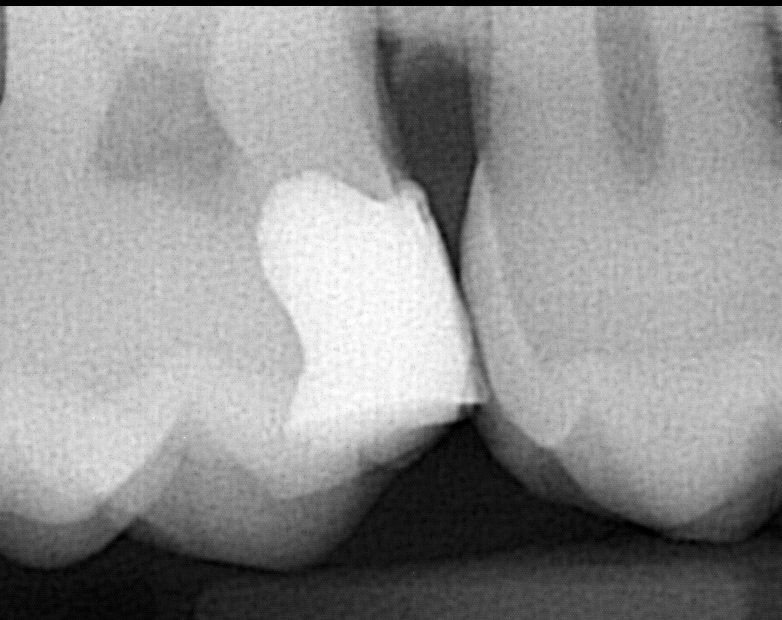

3. The Dental Filling is causing food impaction

When a tooth cavity extends to between teeth, it’s very important to have a filling that makes a tight contact with the tooth next to it. You want the contact to be so tight that you can hear the floss snapping when passing through. If the contact is too wide, the floss is not getting much resistance then food will be getting in between teeth at each meal. This can irritate the gum causing gum discomfort, swelling, or even an abscess.

This dental filling should get redone if possible to make a tight contact between teeth. If for some reason the dental filling material is unable to close the space between teeth, a porcelain crown or onlay maybe needed.